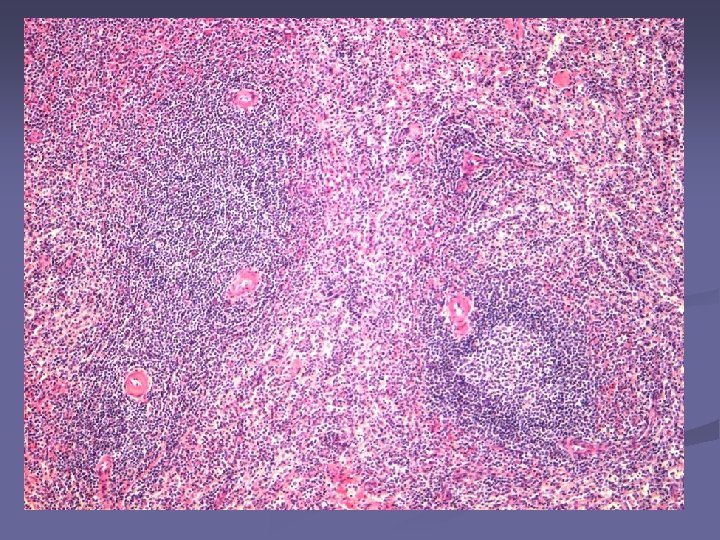

n Pulpa alba Parenchimul - formata din tesut limfoid dens - se organizează in jurul arterelor Rol: procesele imune Pulpa rosie – tesut reticular lax, lacunar, – se organizeaza in jurul sinusurilor venoase. Rol: filtrează sângele Pulpa alba n Pulpa rosie

Splina – col. HE Pulpa alba Pulpa rosie

Structura pulpei albe formata din tesut limfoid dens - se organizează in jurul arterelor Rol: procesele imune n n arteră centrală ţesut limfoid = teaca limfoidă periarterială (PALS)- ly T (in special CD 4, n putine CD 8) n Periferie - Ly B

n La contactul cu atg, ly B se transformă blastic → folicul secundar cu centrul germinativ – pol clar : limfoblaste– spre PR - pol întunecat : plasmocite, ly B memorie – spre a centrală Arteriola va ocupa o poziţie excentrică Structura alcătuită din artera excentrica+ teaca limfoida + foliculul secundar = corpuscul splenic Malpighi (folicul splenic) În PA Limfocitele T in tecile periarteriale(PALS); Limfocitele B - in nodulii limfoizi – in zona marginală (între PA şi PR)